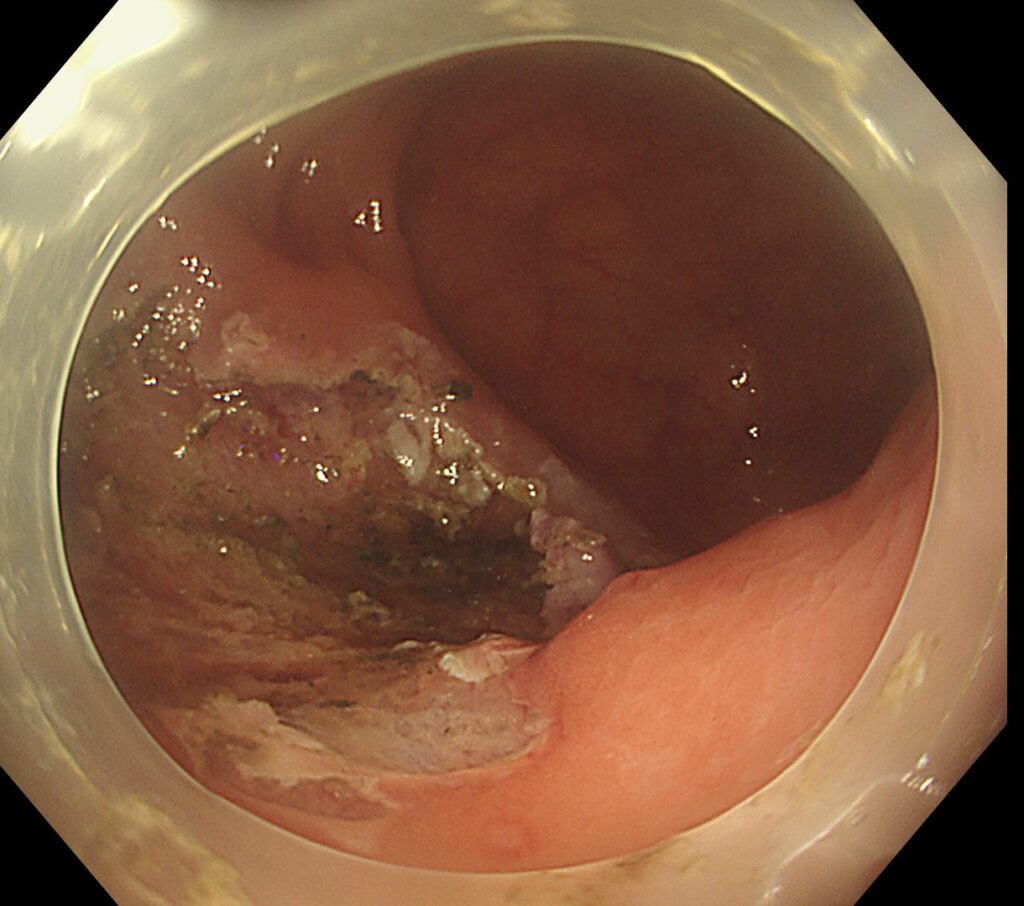

最後に、医療用のクリップで創部を縫縮し終了しました。

病理結果は、内視鏡治療による根治がえられています。

この部位は、手術であれば、人工肛門増設となりうる部位です。内視鏡治療が成功し本当に良かったなと感じた一例です。